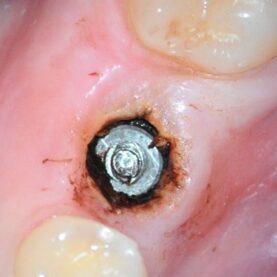

The abutment recovery was routine with reduction of the abutment screw down 3mm to expose the through bore. Next the through bore was tapped to M1.6mm, the distractor bolt was threaded into place and followed by placement of the distractor nut. The fractured conical portion of the abutment was then distracted and recovered. With microscope guidance, the remaining mobile abutment screw fragment was carefully rotated clear of the implant threads and recovered. The implant was cleaned, and the supplied healing abutment was placed finger tight. There was no visible implant damage when examined at 25x magnification. She was referred back to Dr. W. for treatment planning and future restoration.

At the patients request, post clinical appointment and prior to leaving, a detailed conversation was entertained as to why this abutment had failed in such a short time frame. The patient has not needed and therefore has had relatively little dental work to date, so the extraction of #30, implant placement and restoration with failure occurring so quickly, was troubling to her. As I evaluate all the implant abutment fractures in regard to duration in function, location of the fractured component, and the amount of fractured abutment material and type, this case was no exception. While it was no surprise to see another Ankylos abutment fracture on the schedule in a single tooth molar application, the very short time it took to fracture was interesting. The intake form listed this abutment as an Atlantis abutment, but it quickly was apparent this was not the case. The first clue was that tapping progressed rather quickly and while the threads were not deep, a slight eccentricity in the bore allowed for enough thread depth for successful distraction. Once the abutment fragment was recovered, the apical portion of the recovered abutment has a notched geometry as in the top of a castle. This can be appreciated in the above photo of the abutment fragment on the distractor. Ankylos and Atlantis abutments do not have this as the end of their abutments are not notched. This notching is due to a larger diameter through bore which invades the internal wall thickness in the indexing spline areas. While not Ankylos or Atlantis it is consistent for a non-OEM Glidewell abutment and possibly other non-OEM abutments as well. The following photo shows the recovered abutment fragment on the right and an intact Glidewell abutment on the left. Both are on a 1.78mm gage pin which goes completely through the Glidewell abutment and goes into the recovered abutment fragment until it hit a distorted area, secondary to the threading process. The stock Ankylos abutment has a through bore of 1.11mm vs. these at 1.78mm. So, you might say, so what? The problem is the Ankylos abutment has a maximum surface area of just 3.941 mm sq. and is ripe for fracture in this area. For comparison, a Dentsply Astra Tech EV 4.8mm implant and abutment has 9.96 sq.mm. With this Glidewell abutment, the area is reduced to 2.421sq. mm. I have never measured one this small previously. The smallest before this one was the Neodent CM interface, which is a copy of Ankylos for all practical purposes, and also has an enlarged through bore but at 1.51 mm sq. which nets out 3.118 sq.mm. These abutments also break at an accelerated rate. I believe the data is irrefutable. It might be argued this is the circuit breaker in the system to protect against implant fracture. Unfortunately, the analogy is like having a 40-amp circuit with a 5-amp circuit breaker. Almost any load will prematurely shut it down needlessly. She mentioned that a night guard was suggested. While this may help if she bruxes at night if she was able to engage posterior interferences and no anterior guidance, however, it will not protect her from loading secondary to mastication. I did not see an abundance of pathway wear to suggest a significant bruxing habit, nor did I see lateral excursive interferences. The only way I see to improve the stability of this implant / abutment connection is to use a solid abutment. This abutment will get the abutment cross section up to 4.91 mm sq. While this may work for a while, and clearly better than what was in previously, she has to understand two facts. One, I have recovered many fractured solid abutments as well, possibly 20 two-piece Ankylos abutments to one solid in approximately 220 fractured Ankylos abutment cases to date but recovering a solid is significantly more difficult to do without implant damage. Therefore, by restoring with a solid abutment it does not mean fracture is off the table. Unfortunately, I don’t have a better, simpler solution for this situation as the adjacent teeth are in good shape. I have been involved with three similar cases where the patient fractured a solid abutment rather quickly and the only real solution was to replace the implant with one that has a more overall robust mechanical connection such as a 4.8 EV.